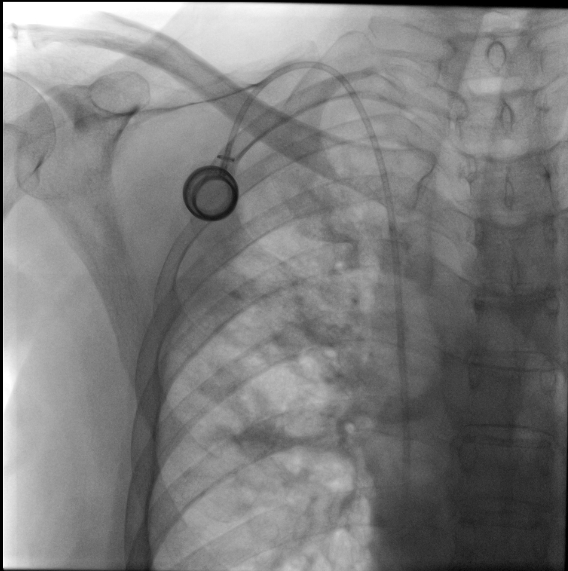

She went to emergency department a month after finishing Durvalumab because of purplish face and edema. Also she had problems with swallowing. No fever nor other symptomatology appeared. Blood tests and X ray were done (Table 1). Ten days before, subcutaneous device for treatment was implanted. Chest X-ray control was normal (Figure 1).

Figure 1 Chest X-ray control after implant of subcutaneous device. No radiological changes or patologic signs were present.